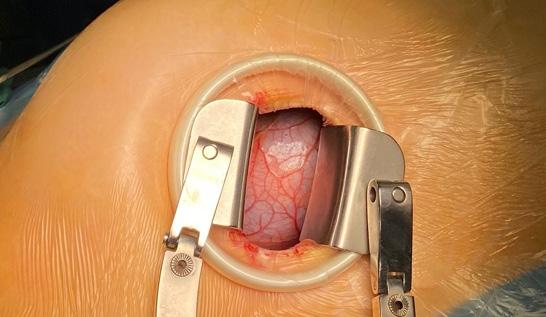

Minitoracotomia dreaptă

Pacientul este plasat în decubit dorsal cu umărul drept ușor ridicat; este anestezi at și intubat cu sondă dublu lumen care să permită ventilația selectivă pulmonară. Se introduce o sondă de ecocardiografie tran sesofagiană (ETE) cu ajutorul căreia se confirmă diagnosticul preoperator și me canismul patologiei mitrale, se ghidează canularea periferică pentru circulație ex tracorporală (CEC) și se evaluează funcția cadiacă și calitatea gestului asupra VMi. Pacientul este rotat 30 grade către stânga, efectuându-se o toracotomie antero-la terală de 5-7 cm în al IV-lea spațiu inter costal. Rotirea pacientului către stânga nu este obligatorie, multe centre renunțând la această abordare, din cauză că inima se îndepărtează de toracele drept. În schimb, este important ca brațul drept să fie flectat la 120 grade și în ușoară abducție, pentru a se îndepărta de viitoarea incizie (Fig.1,2).

Hemostaza minuțioasă la nivelul pere telui toracic este esențială. După efectuarea toracotomiei, se folosește un depărtător de

tip “Alexis soft tissue retractor”, dublat de un depărtător standard dacă se folosește tehnica vizualizării directe (Fig.3). Managementul chirurgical al circulației extracorporale

În continuare, se efectuează două bur se la nivelul aortei ascendente, sprijinite pe petece, pentru canula de cardioplegie anterogradă. Este important de mențio nat că efectuarea bursei de cardioplegie și introducerea canulei trebuie să se facă după inițierea CEC și golirea cordului, facilitând astfel expunerea aortei ascen dente și evitând lezarea urechiușei drepte (Fig.12).

Urmează clamparea aortei ascenden te, care se realizează prin contraincizie în cazul clampului Chitwood (Fig.14).

După terminarea cardioplegiei și ob ținerea asistolei, se incizează atriul stâng la nivelul șanțului interatrial disecat și se montează un aspirator intraatrial (Fig.13).

De îndată ce expunerea valvei mitrale este obținută cu ajutorul unui depărtă tor auto-static, se începe inspecția valvei (Fig.14).

În concluzie, abordul minim invaziv al valvei mitrale prin minitoracotomie dreaptă, folosind tehnica vizualizării di recte, oferă o vizualizare excelentă a aces teia. Urmând pașii simpli descriși mai sus, valva mitrală poate fi expusă corect, facil și fără incidente, urmând apoi pașii clasici ai plastiei/protezării acesteia.

Fig.3. Minitoracotomie în spațiul IV intercostal drept – tehnica vizualizării directe Fig.4. Incizia de expunere

a vaselor

femurale comune

drepte imediat

sub ligamentul inghinal Fig.2. Toracotomie antero-laterală dreaptă de 6 cm, pentru acces cu vizualizare directăFig.1. “Set-up” pentru abordul chirurgical minim invaziv al valvei mitrale Fig.5. Descoperirea feței anterioare a arterei si venei

femurale

comune drepte Fig.6.

Control

ETE

intraoperator

– ghid

prezent

în

aorta descendentă toracică

Fig.7. Control ETE intraoperator – ghid prezent în atriul drept Fig.8. Control ETE intraoperator – canulă la nivelul atriului drept Fig.9. Canularea vaselor femurale comune drepte – aspect final

Fig.10. Suspendarea pericardului sub circulație extracorporală

Fig.11. Disecția șanțului interatrial sub circulație extracorporală Fig.12. Introducerea canulei de cardioplegie în aorta ascendentă Fig.13. Incizia atriului stâng și introducerea unui aspirator intracavitar Fig.14. Dublă leziune mitrală – expunere minim invazivă prin vizualizare directă